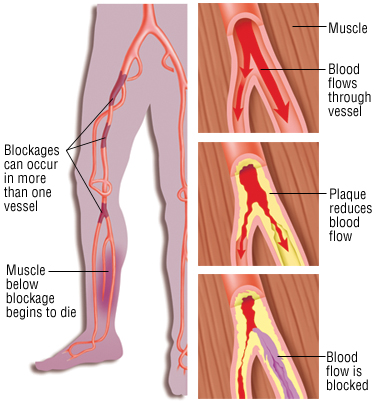

Ως ισχαιμία κάτω άκρων ορίζεται η μείωση ή διακοπή της ροής του αίματος στα κάτω άκρα λόγω κάποιας βλάβης ή απόφραξης στις αρτηρίες που το τροφοδοτούν. Πρόκειται για μία επικίνδυνη κατάσταση που ειδικά στα τελευταία στάδια της μπορεί να οδηγήσει ακόμα και σε γάγγραινα ή απώλεια του μέλους που πάσχει.

- Χρόνια στένωση των αρτηριών των άκρων η οποία προοδευτικά επιδεινώνεται και καταλήγει σε απόφραξη της αρτηρίας

κάτω άκρα και αποφράσσει κάποια αρτηρία. Εμβολή μπορεί να έχουμε και από υλικό ανευρύσματος κοιλιακής αορτής ή λαγονίου ή ιγνυακής αρτηρίας (αθηροεμβολισμός) - Θρόμβωση. Σε ήδη ανεπτυγμένη αθηρωματική πλάκα μιας αρτηρίας των κάτω άκρων αναπτύσσεται πάνω της θρόμβος, ο οποίος την αποφράσσει 100%

Συμπτώματα

- προοδευτικά αυξανόμενος πόνος στο πάσχον σκέλος κατά τη βάδιση ο οποίος επιδεινώνεται ακόμα και σε λίγα μέτρα βάδισης

- πόνος το βράδυ κατά τη κατάκλιση κυρίως στα δάκτυλα ή την πτέρνα

- αδυναμία στο πάσχον μέλος

- τροφικές αλλοιώσεις – ατροφία

- αίσθημα ψυχρότητας στο πάσχον μέλος και γάγγραινα δακτύλων ή πτέρνης

- Σε περιπτώσεις οξείας ισχαιμίας, αιφνίδια και προοδευτική απώλεια της αισθητικότητας και της κινητικότητας του πάσχοντος σκέλους.